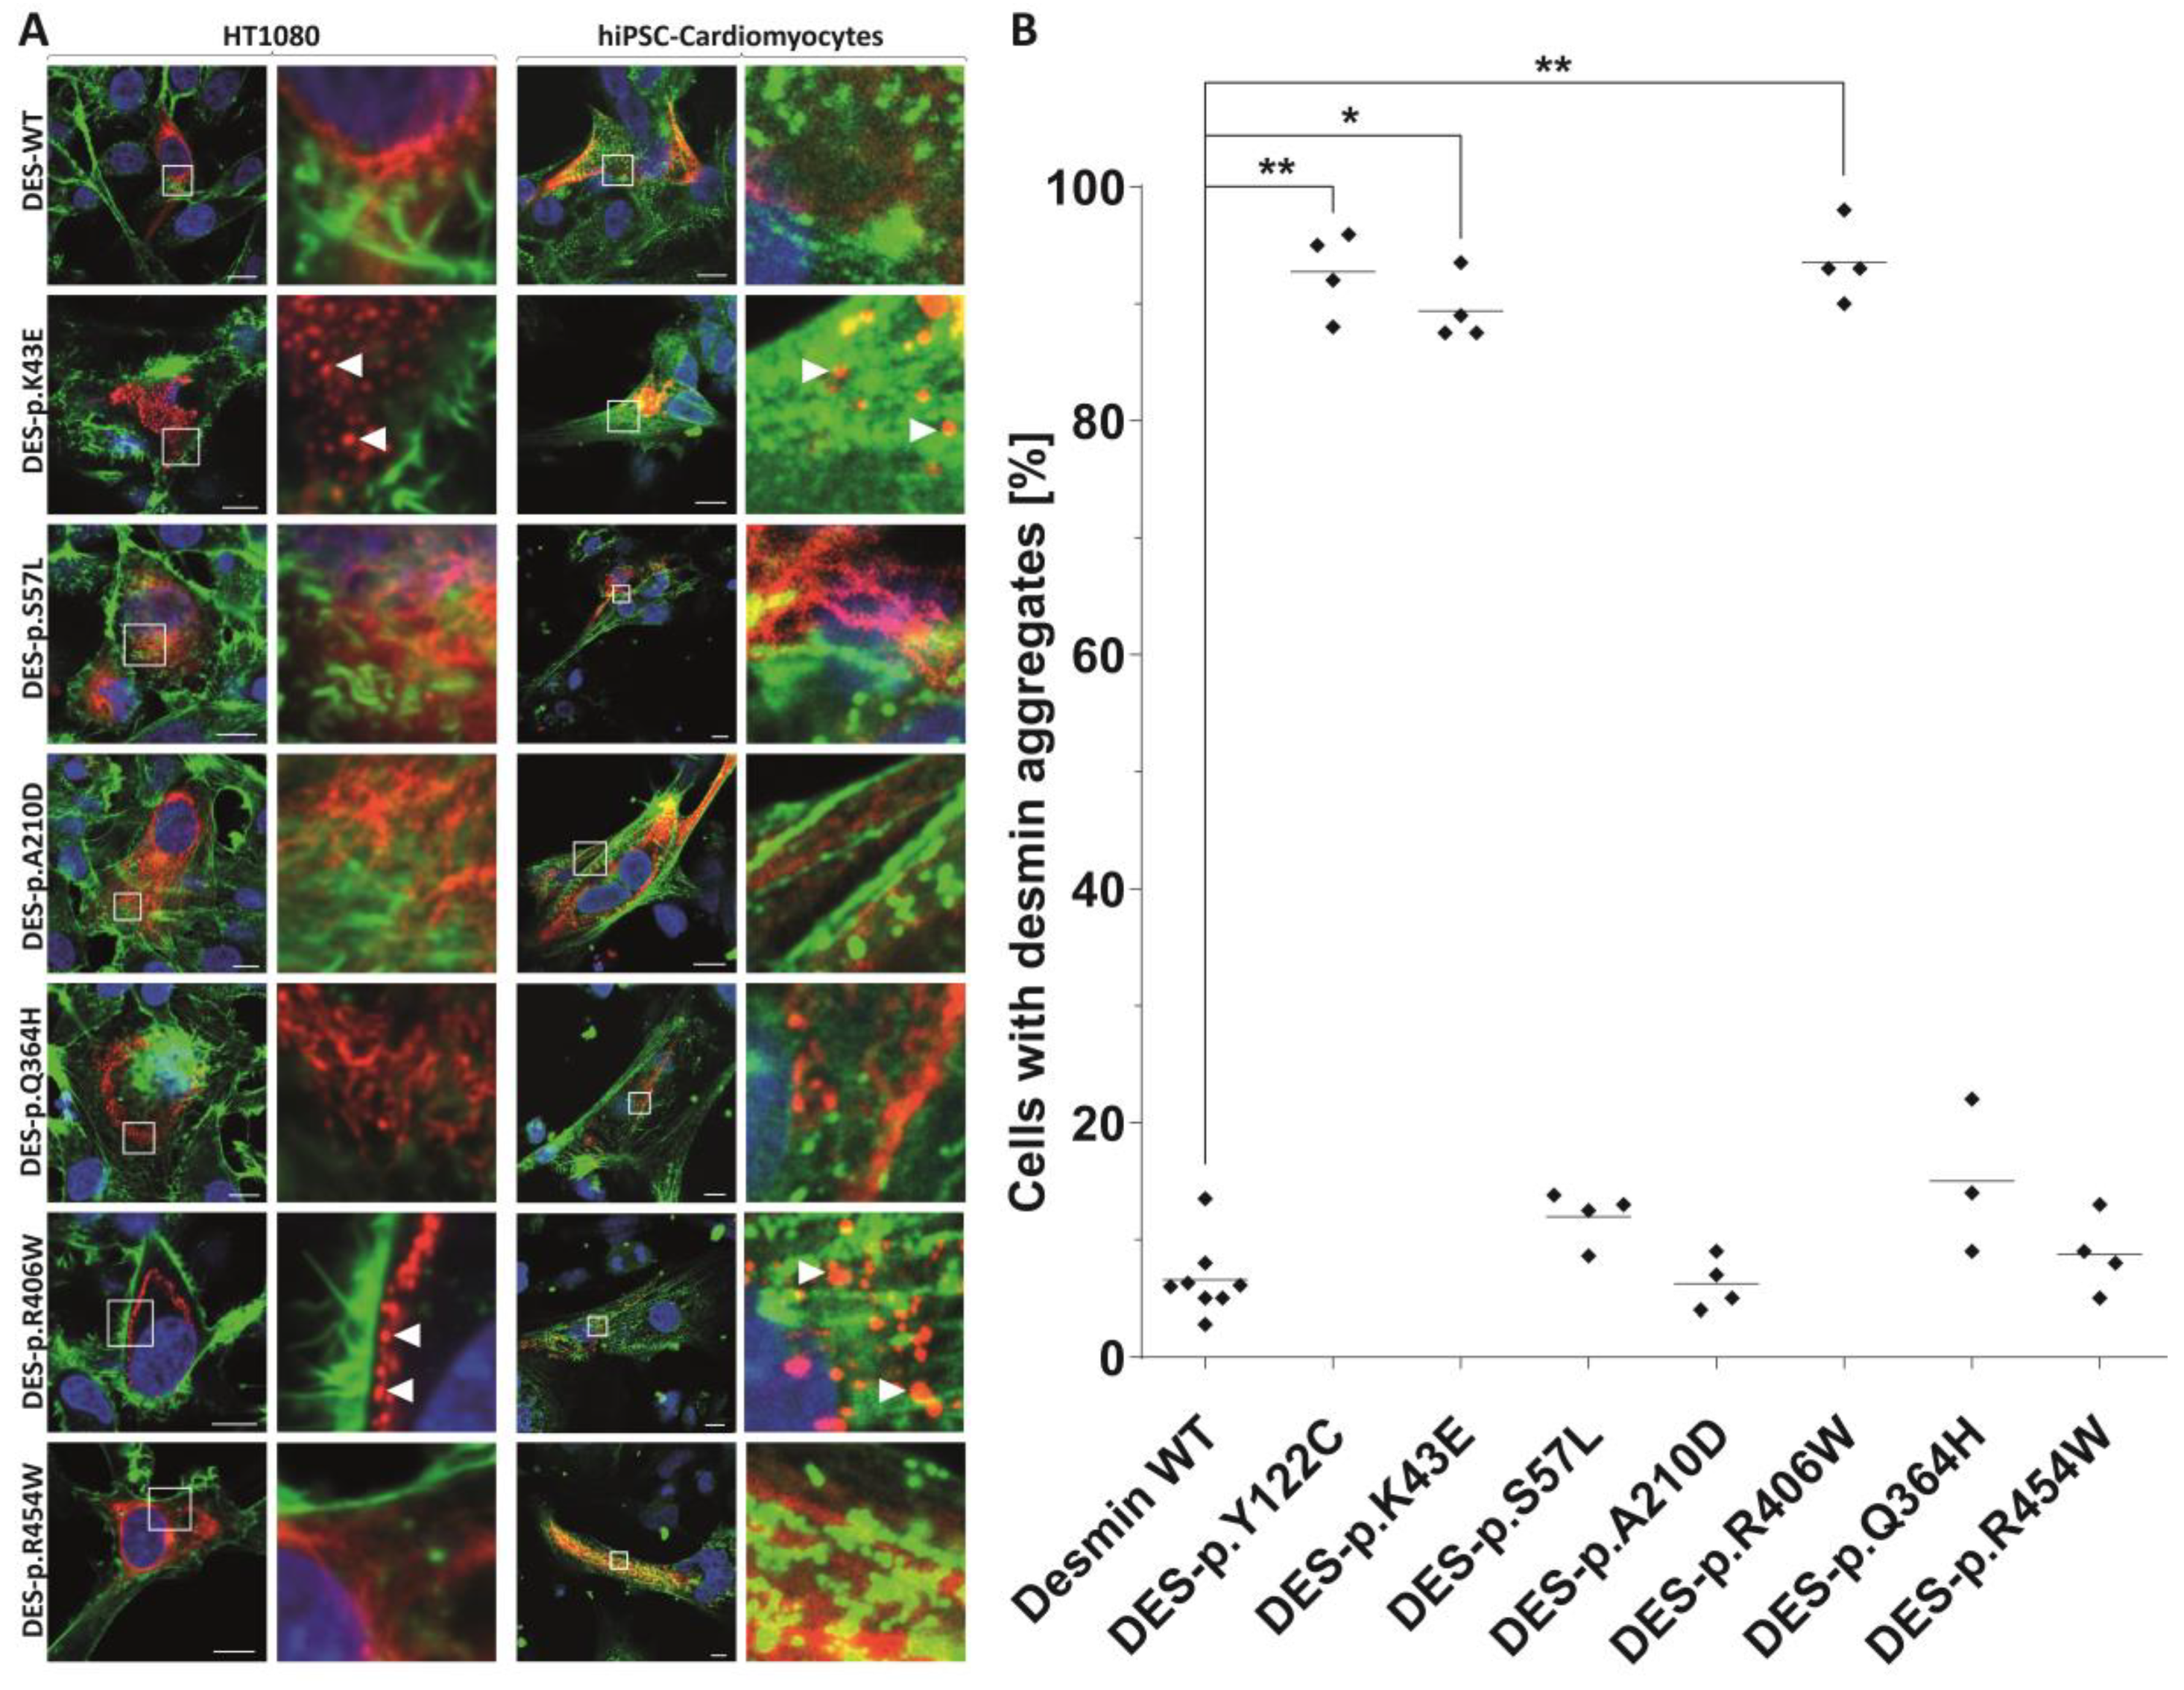

2.3. In Vitro Analysis of DES Variants

2.4. Statistical Analysis of Aggregate Formation

3.4. Indications for the Pathogenicity of the Novel Desmin Variants